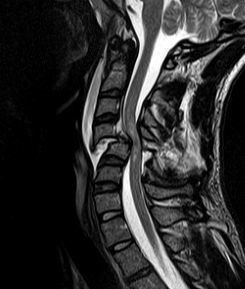

1. secundario a lesion en la medula espinal a nivel cervical o toracico alto (T6)